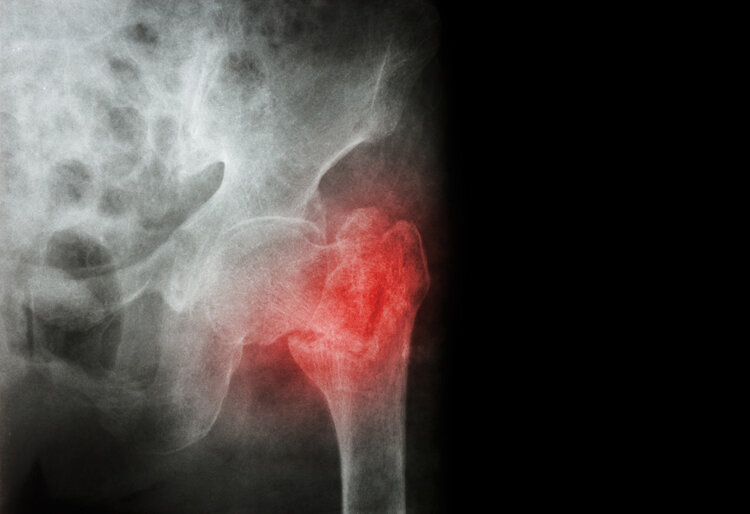

若老年人长期钙不足很容易导致骨密度下降,引起牙齿松动、骨骼老化等问题,关节部位会因为钙不足而容易患上关节病,同时会增加老年人骨质疏松的发生几率,严重时甚至有骨折的风险!